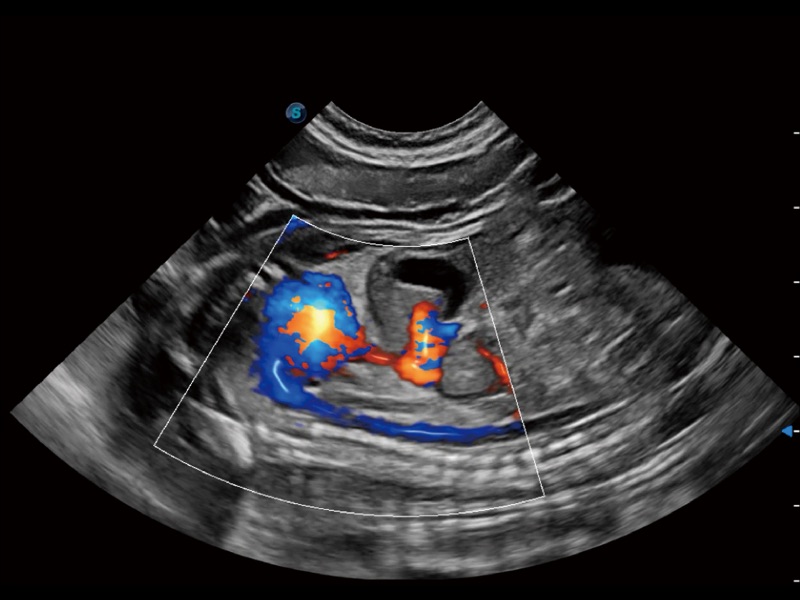

通過360度任意調(diào)節(jié)3條M型取樣線,在同一心動周期上觀察心臟不同位置的運(yùn)動曲線,得到準(zhǔn)確的心功能測量數(shù)據(jù),有效評估心肌運(yùn)動及左心室功能。

實(shí)時(shí)用顏色表示心肌組織運(yùn)動,觀察和定量組織的運(yùn)動情況,對快速檢測與評估心肌的灌注和活性、電傳導(dǎo)及心肌收縮和舒張功能等均能提供重要的診斷信息。